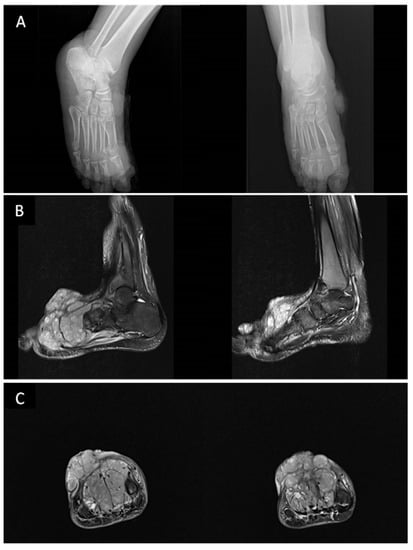

6.3. Musculoskeletal Skeletal Involvement

- Caponetti, G.; Dezube, B.J.; Restrepo, C.S.; Pantanowitz, L. Kaposi sarcoma of the musculoskeletal system: A review of 66 patients. Cancer. 2007, 109, 1040–1052. [Google Scholar] [CrossRef]

- Restrepo, C.S.; Martínez, S.; Lemos, J.A.; Carrillo, J.A.; Lemos, D.F.; Ojeda, P.; Koshy, P. Imaging manifestations of Kaposi sarcoma. Radiographics 2006, 26, 1169–1185. [Google Scholar] [CrossRef]